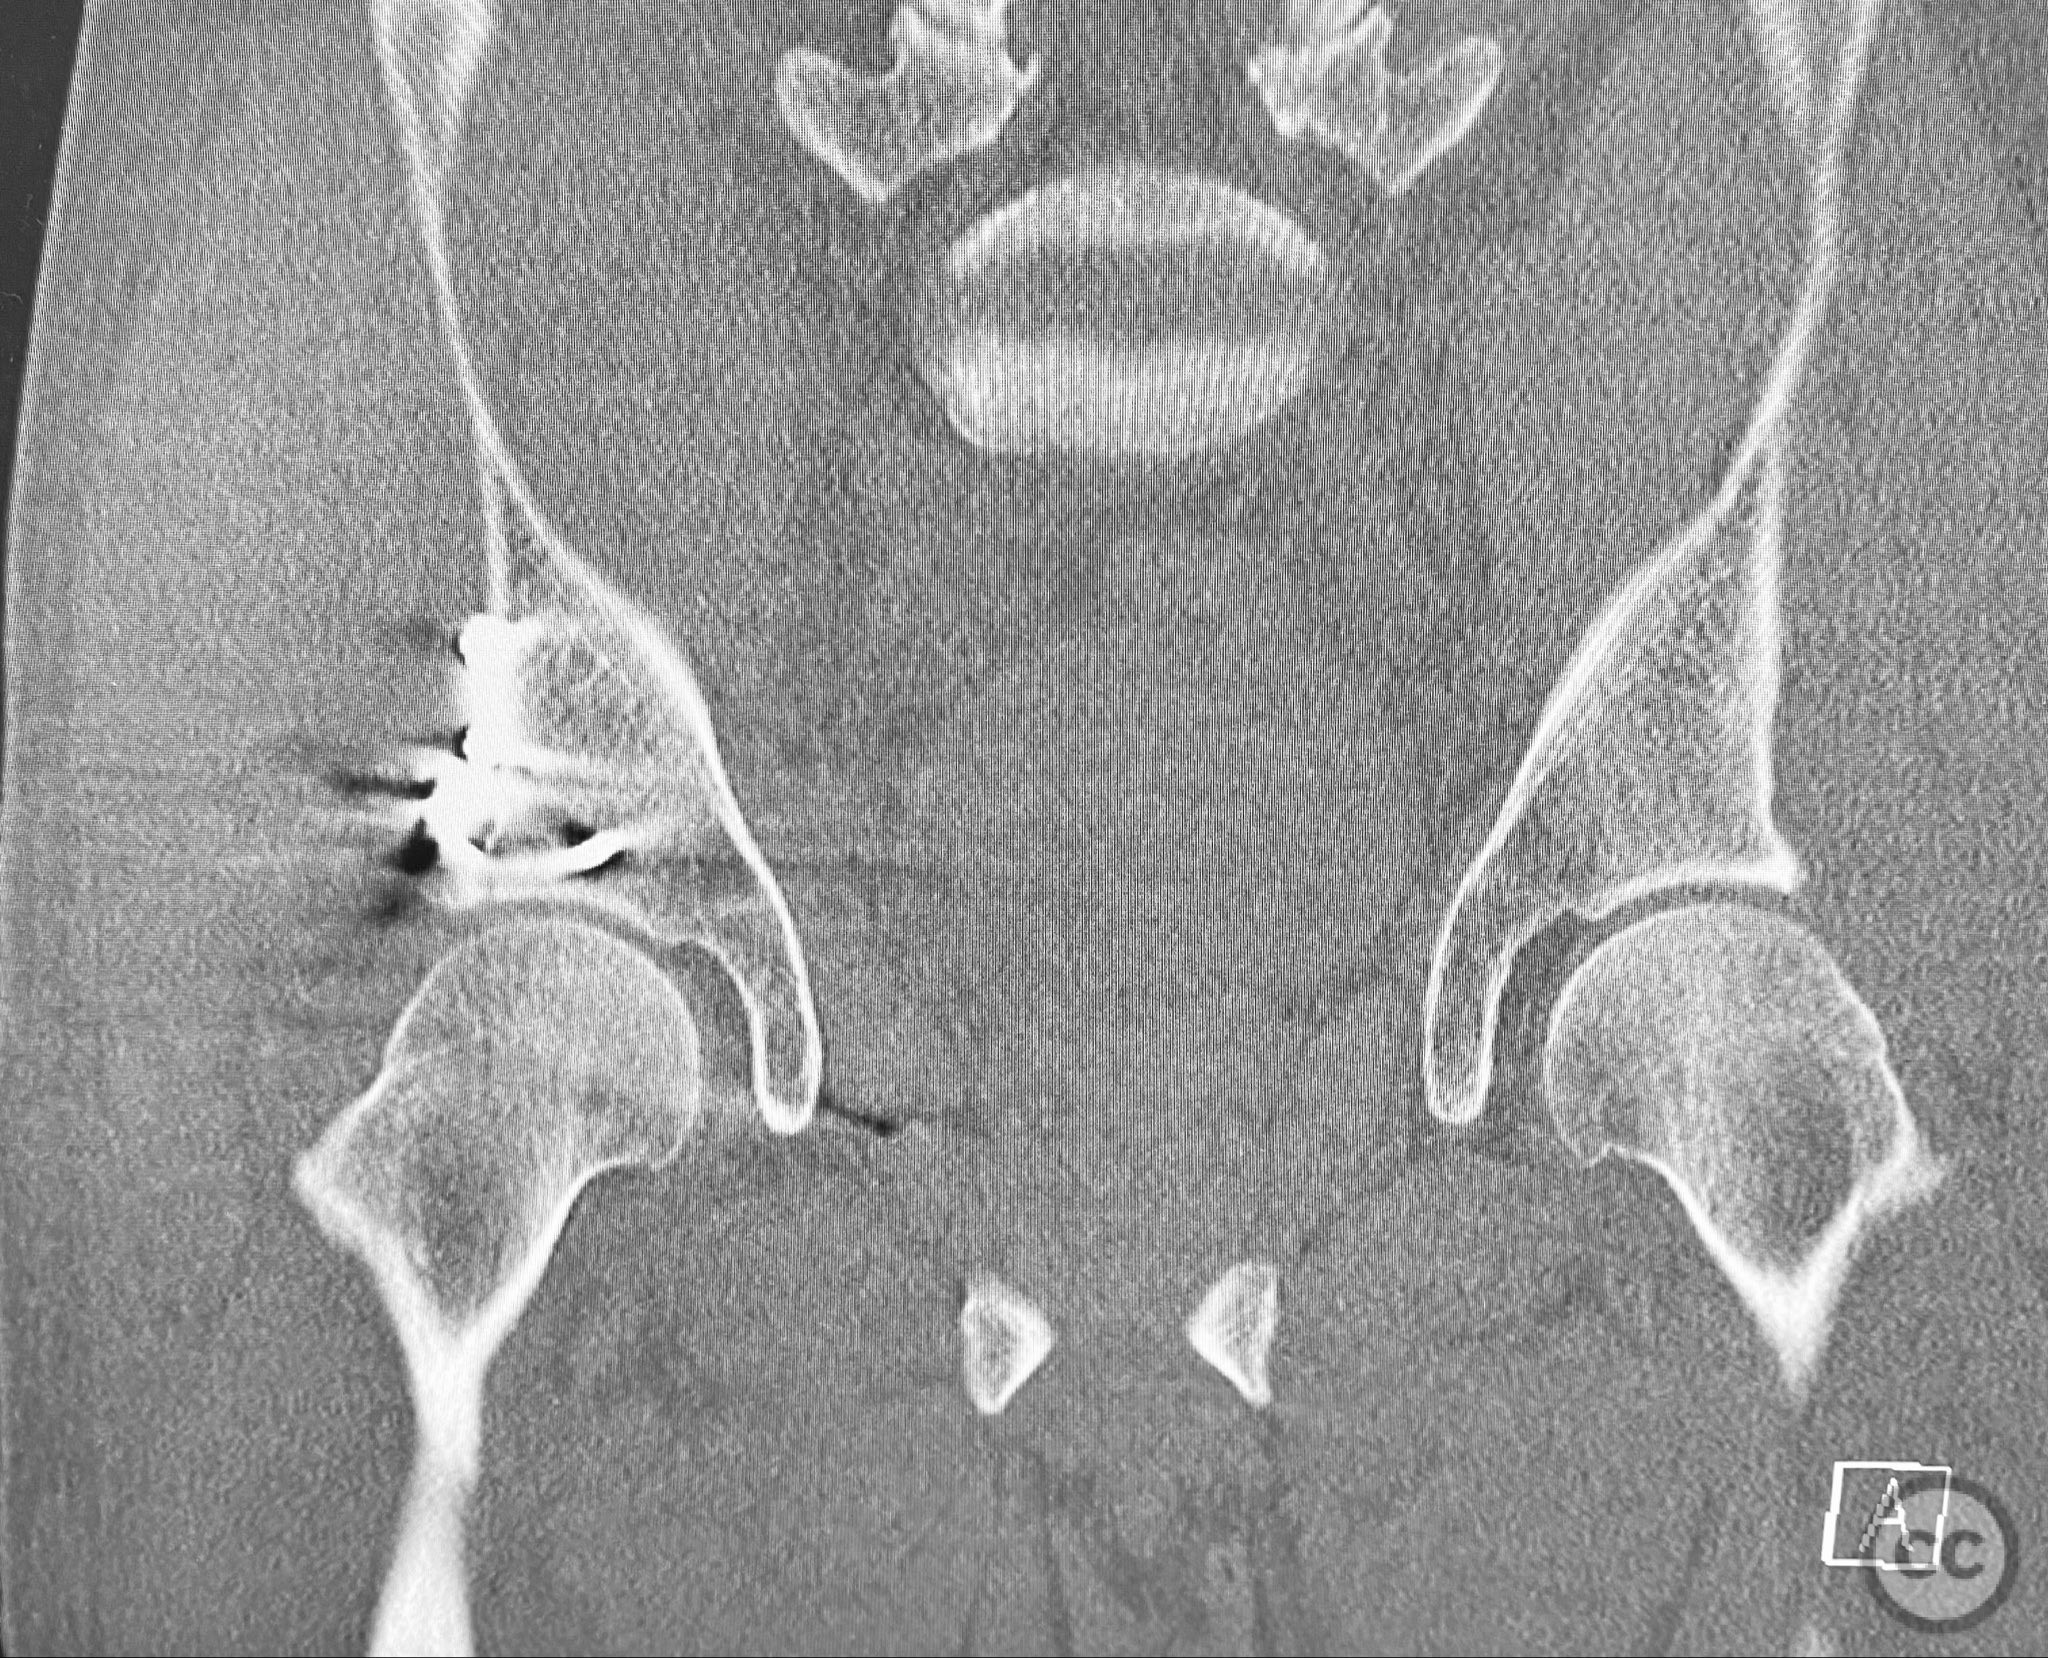

Planning remarks:  The preoperative plan included advanced imaging with CT, including 3D surface renderings, to further delineate the extent of articular impaction, wall fragment size, and comminution. The plan was for open reduction and internal fixation via a posterior Kocher-Langenbeck approach in the prone position. Elevation of impacted articular segments was planned, with structural support using autologous bone graft harvested from the greater trochanter. Fragment-specific fixation was planned with a spring hook plate for the cranial wall fragment and a reconstruction plate for the main posterior wall fragment.

The initial failed closed reduction likely resulted from interposed soft tissue or bony fragments, or inadequate sedation/muscle relaxation. Repeat reduction under improved conditions was successful prior to definitive fixation. 3D CT renderings provided enhanced visualization of impaction zones and comminution, facilitating preoperative planning for grafting and fragment-specific fixation. Intraoperatively, elevation of the impacted dome required careful manipulation to avoid further chondral injury. Use of a spring hook plate provided secure fixation of the cranial wall fragment, while the reconstruction plate supported the main wall fragment. Postoperative CT confirmed satisfactory reduction and implant positioning.